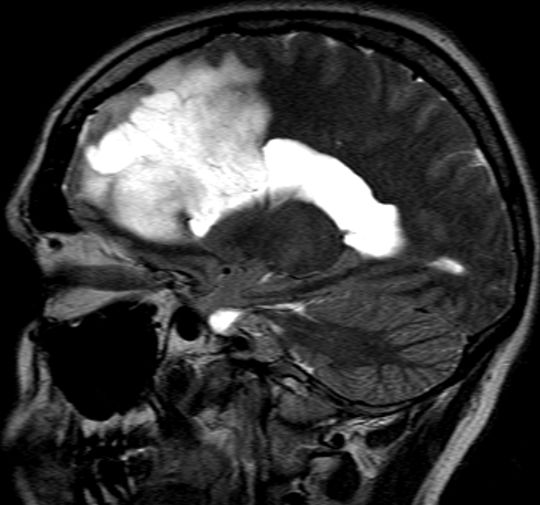

| Astrozytom II | 33jährige Frau mit einem links-frontalen Gliom Grad 2.![]()

![]() | |||||||||||||||||||||||||||||||||||||||||||||||||